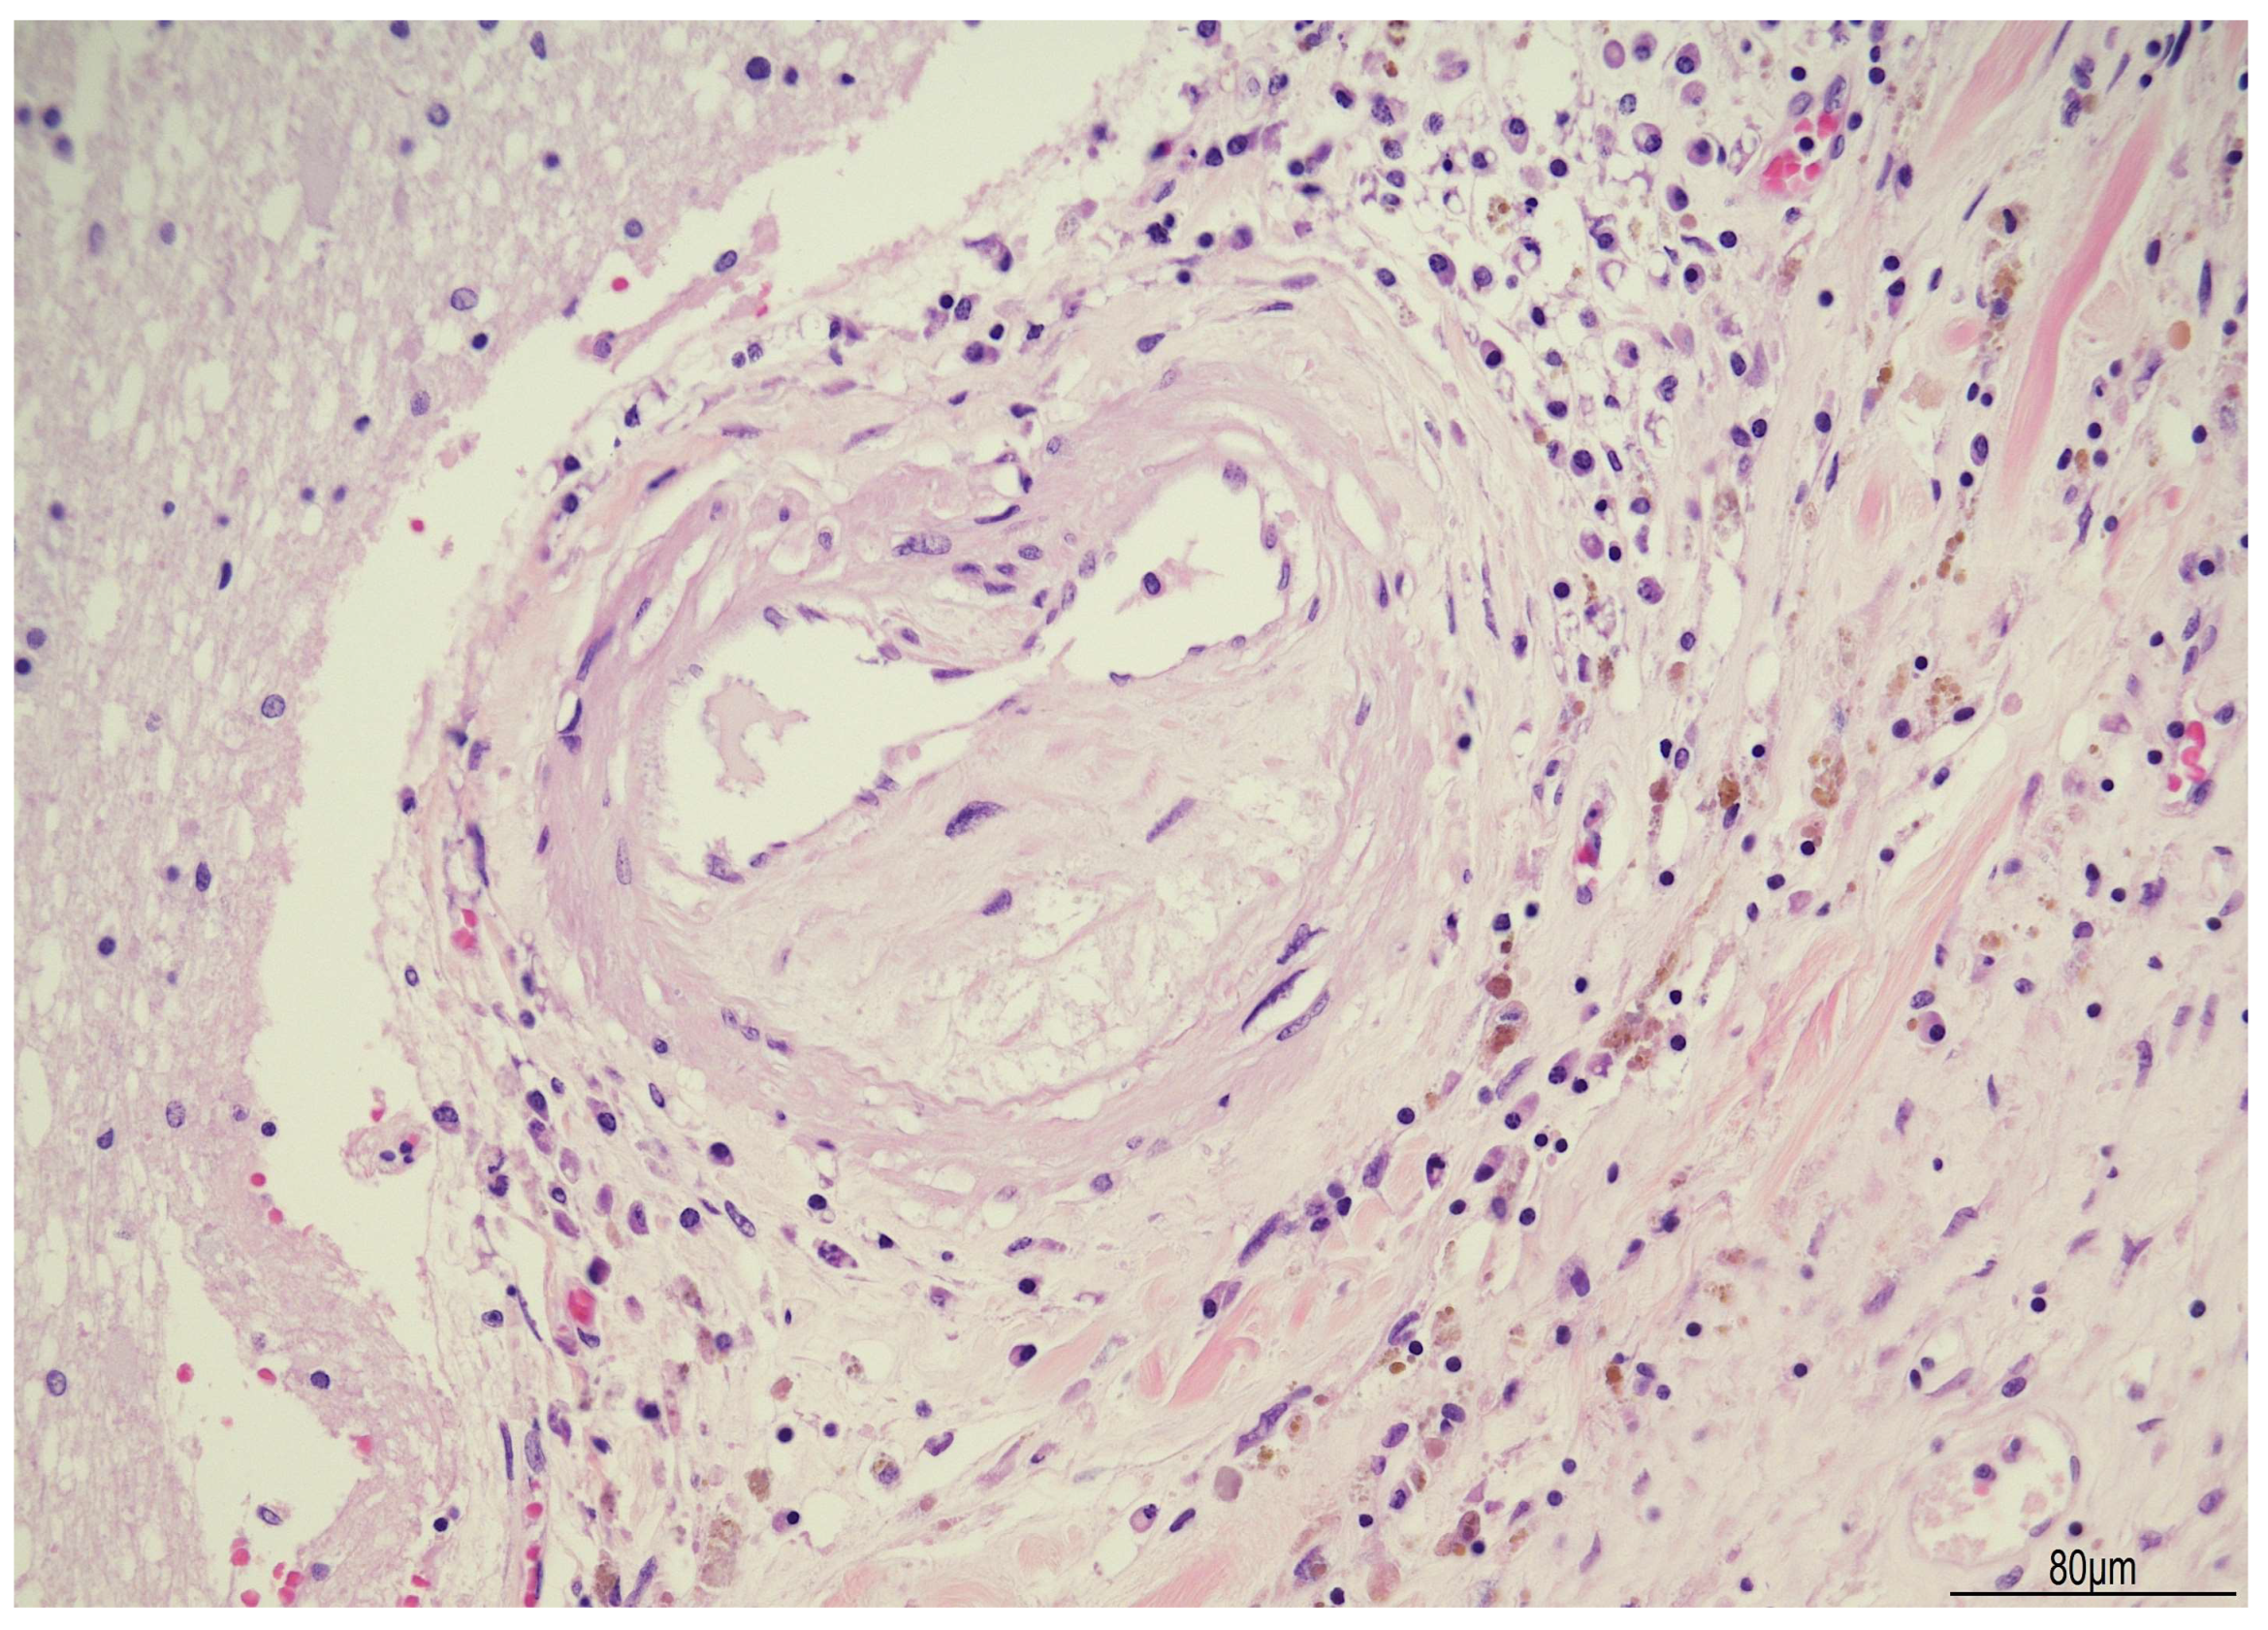

2.1. Autopsy Findings

| ~3 months after surgery | Progressive neurological decline, coma, death | Autopsy: PAS-D and GMS stains positive for fungal elements (Candida albicans) | – | Supportive intensive care until death |